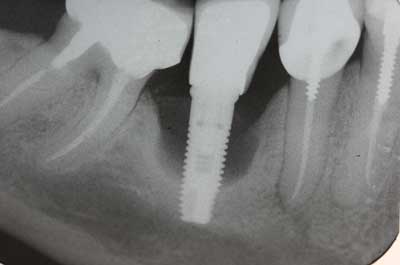

La respuesta larga es un poco más interesante. Los implantes dentales no son infalibles. De hecho, la estadística oficial dice que el 97% de los implantes tienen éxito. Eso suena muy bien, pero hay que decir que ese porcentaje suele referirse a “casos ideales”.

Si bien nos encontramos con muchos casos ideales, el resto son pacientes con retos mayores: problemas de salud sistémicos, diabetes, mala calidad ósea, atrofia de los maxilares o mala cicatrización. Cuando analizamos únicamente este universo de pacientes con más retos, el porcentaje de éxito puede disminuir considerablemente hasta un 60%.

El expertise y la tecnología: Aquí entra la selección de materiales, las técnicas quirúrgicas, el equipo médico y, por supuesto, la experiencia del especialista en implantes.